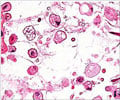

This medication is an enzyme, prescribed for long-term enzyme replacement therapy (ERT) for pediatric and adult patients with type 1 Gaucher disease. It helps to decrease the harmful effects of the disease by breaking down glucocerebroside.When should Velaglucerase Alfa for Injection not be taken? (Contraindications)